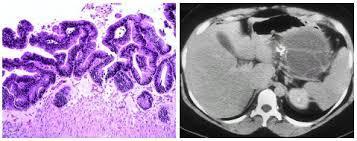

Question 3

Question

A un paciente con colitis ulcerosa con afectación hasta el colon transverso se le realiza una colonoscopia de cribado de cáncer colorrectal. La colonoscopia no muestra signos de actividad inflamatoria. Se realizaron múltiples biopsias cada 10cm. Las biopsias fueron revisadas por 2 patólogos expertos demostrando un foco de displasia de alto grado en una de las biopsias realizadas en el colon sigmoide. ¿Qué indicaría a continuación?

Answer

• Repetir la colonoscopia para confirmar el diagnóstico.

• Vigilancia intensiva con colonoscopia cada 3-6 meses.

• Repetir la exploración y realizar una cromoendoscopia para identificar la lesión .

• Proctocolectomía total.

• Tratamiento con mesalazina a dosis de 2-3 gramos al día y repetir la exploración a los 3 a 6 meses.